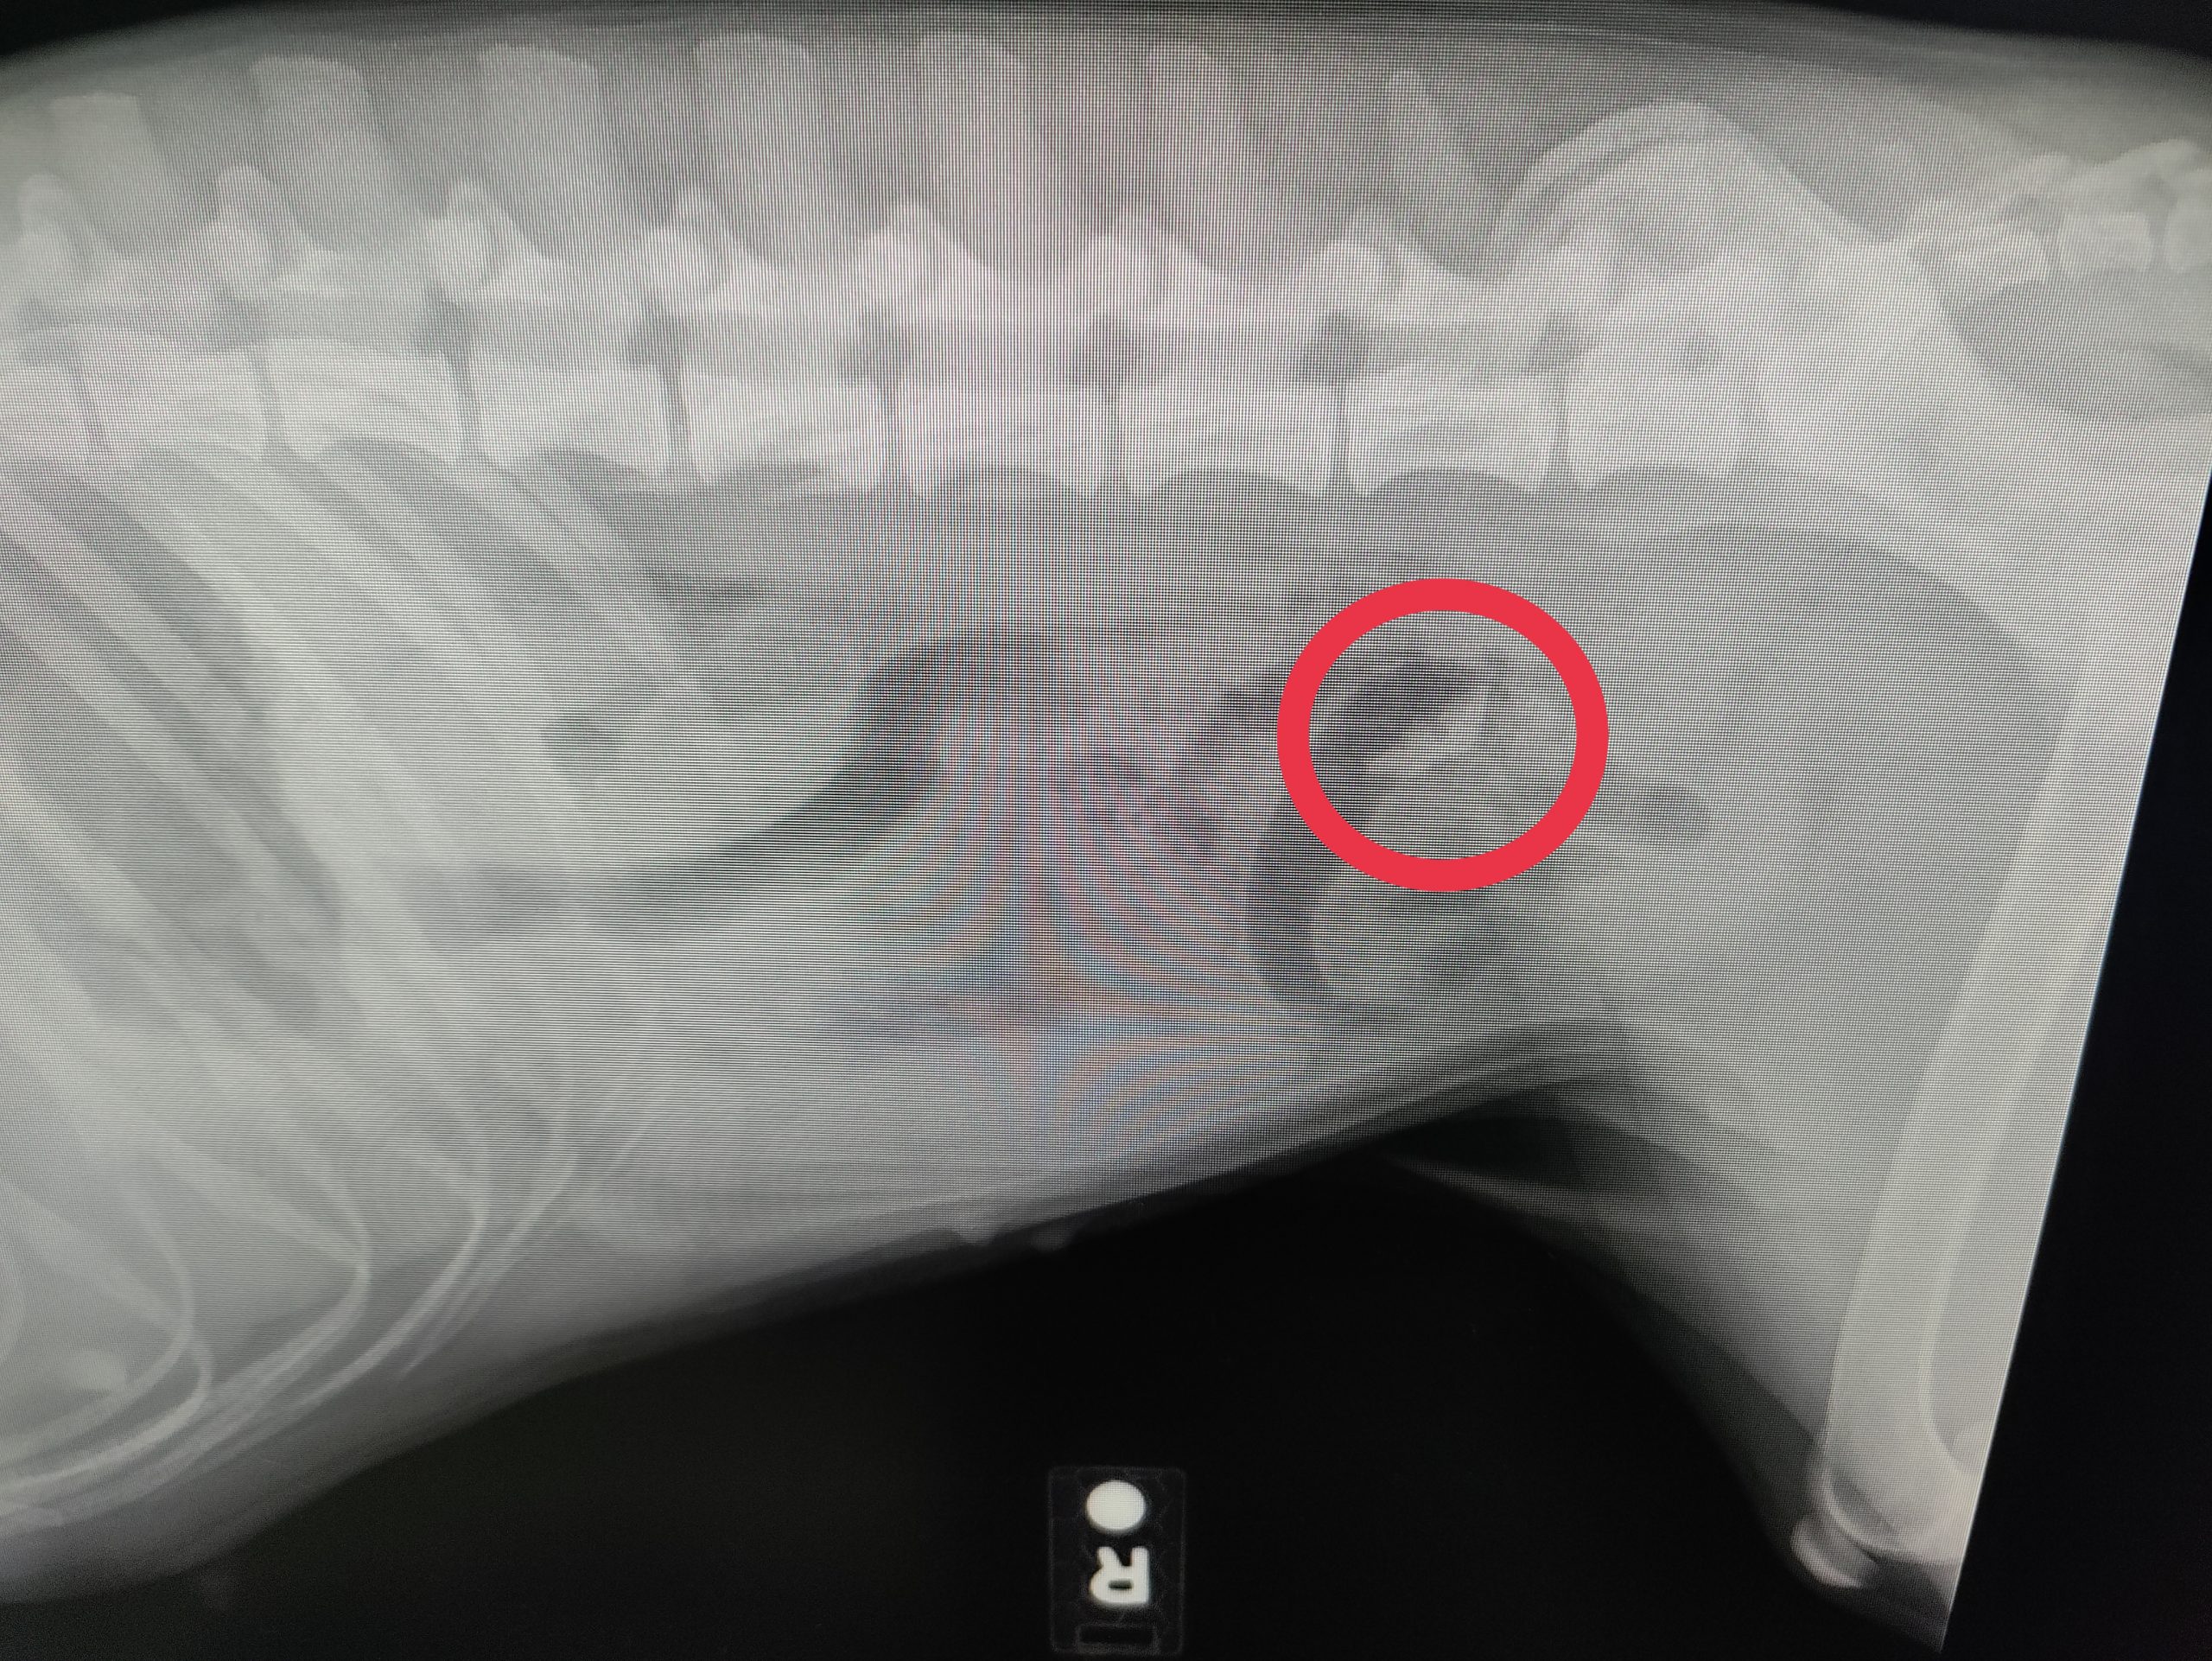

Cassie Obstruction Episode

She ate something, I suspect the squeaker from a toy recently destroyed, and it blocked up her insides. So she […]